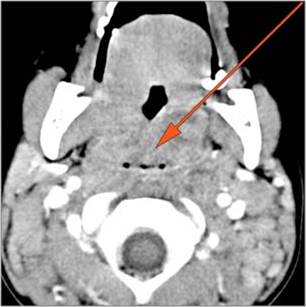

9 month old male presenting to the emergency room with poor feeding, fever, respiratory distress and possible retropharyngeal abscess or suppurative retropharyngeal adenitis.Exam

There is reactive retropharyngeal lymphadenopathy. |

Yes | NA |

There is suppurative retropharyngeal lymphadenopathy. |

If there is suppurative retropharyngeal adenopathy what is the maximum short axis dimension of the largest suppurative node. Measurement |

< 2cm | NA |

There is edema/abscess within the adjacent parapharyngeal and retropharyngeal spaces. |

Pharyngitis with suppurative retropharyngeal adenitis.